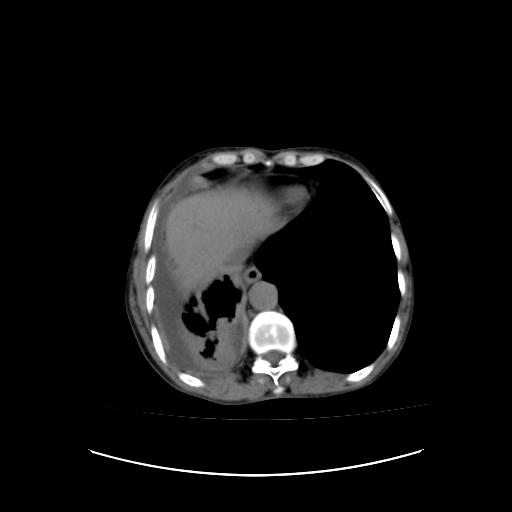

可见多发肺内病灶,且胸膜病灶较多有圆球状而非丘状,多考虑胸膜转移瘤伴胸腔积液,右侧胸廓缩小固定,且部分病灶呈丘状,尚不除外恶性胸膜间皮瘤伴肺内转移

恶性胸膜间皮瘤伴肺内转移可能性大;或胸膜、肺内均为转移瘤,左肺下叶亦见多发小结节影。

右侧胸廓塌陷,右侧胸膜广泛增厚并见多发胸膜结节,右侧少量胸腔积液并包裹。

胸膜转移瘤  包裹性胸腔积液  肺内转移

右胸腔结节均考虑来自胸膜(部分来源于叶裂),考虑胸膜间皮瘤或转移瘤.